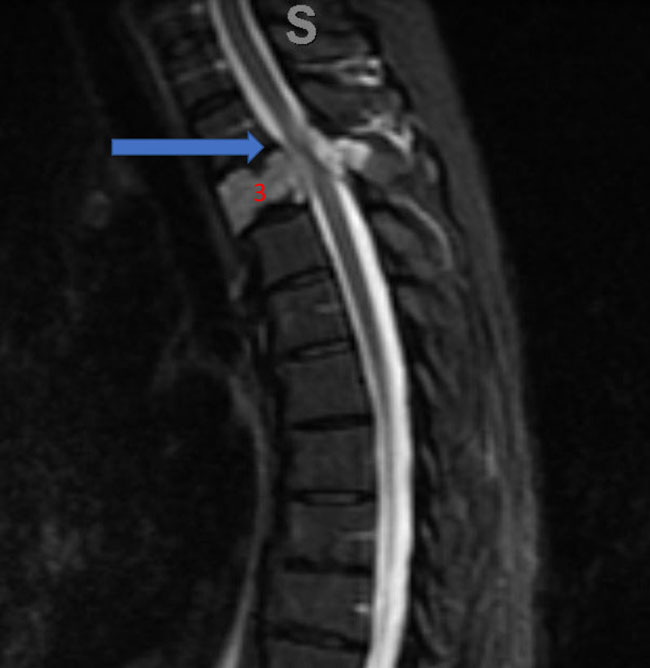

Spinal angiography showed a very hypervascular lesion fed predominantly by the right supreme intercostal artery (Figure 2. A, B).

Figure 2. (A, B) Selective angiography of the right supreme intercostal artery demonstrates extensive hypervascularity of this aggressive T3 hemangioma.